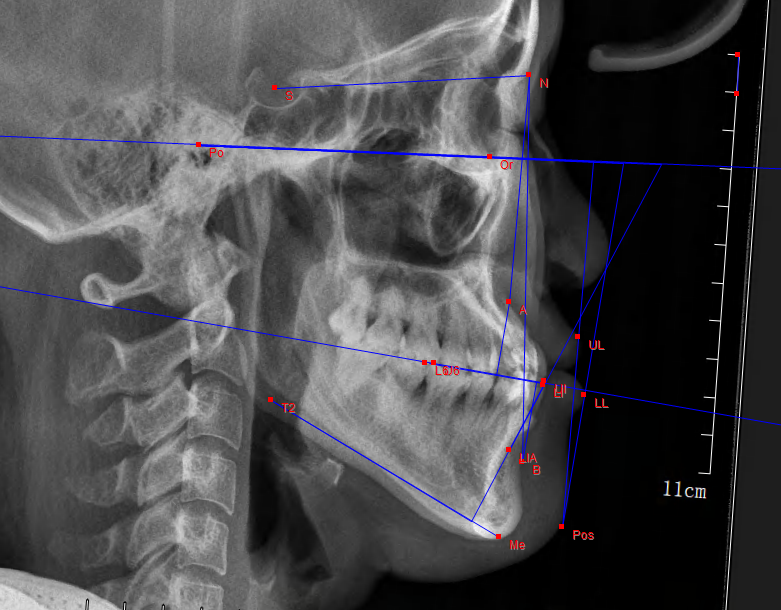

一、X線頭型測(cè)量片

可以讓醫(yī)生了解到牙頜顱面的發(fā)育情況,將診斷從表面觀察,深入到對(duì)整個(gè)骨骼的判斷,做到精準(zhǔn)定位、測(cè)量、制定矯治計(jì)劃。